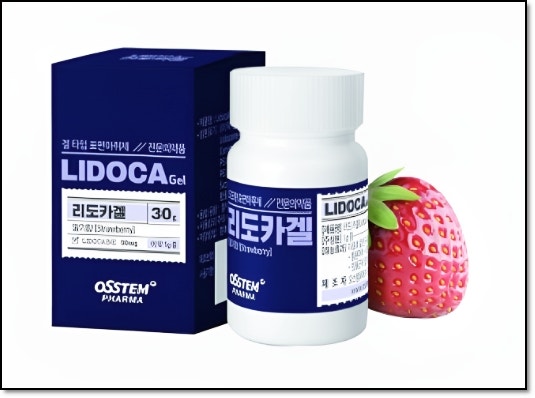

반갑습니다. 치의학 박사 장영준입니다. “사랑니 발치를 해야된다는데.. 너무 아플까 봐 걱정돼요..” 이 글을 읽으시는 분들은 안산사랑니치과 발치가 가능한 곳을 찾으시다가 이 글을 클릭해주셨을 것 같은데요.